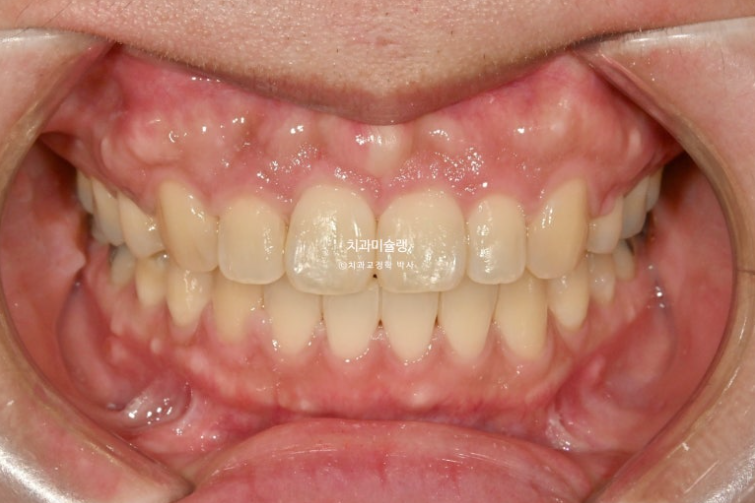

Finally, three years after treatment began, the appliances were removed and treatment was completed.

The bone in the gum area above the front teeth looks uneven, right?

The midline and deep overbite have improved.

A stable, secure occlusal relationship is a given.

Let’s compare the before and after.

If you compare the before-and-after photos, you can see that the previously flat gum area above the front teeth has become uneven.

It is easy to misunderstand this as bone growing and protruding more than before, but in fact, the protruding part is the original position of the bone from before treatment, when the gums were protruding.

When the front teeth are successfully moved backward, including the roots, the gum bone covering the tooth roots also naturally resorbs and moves backward together with the roots. This is the process by which gum protrusion is resolved.

However, some areas of gum bone stubbornly remain in their original position and do not resorb.

As a result, these areas can look relatively protruded compared with the surrounding area after treatment, and this is the reason why the gums sometimes look uneven after extraction orthodontics.

There is no need to worry too much. Over time, most of it naturally becomes flatter through bone remodeling.